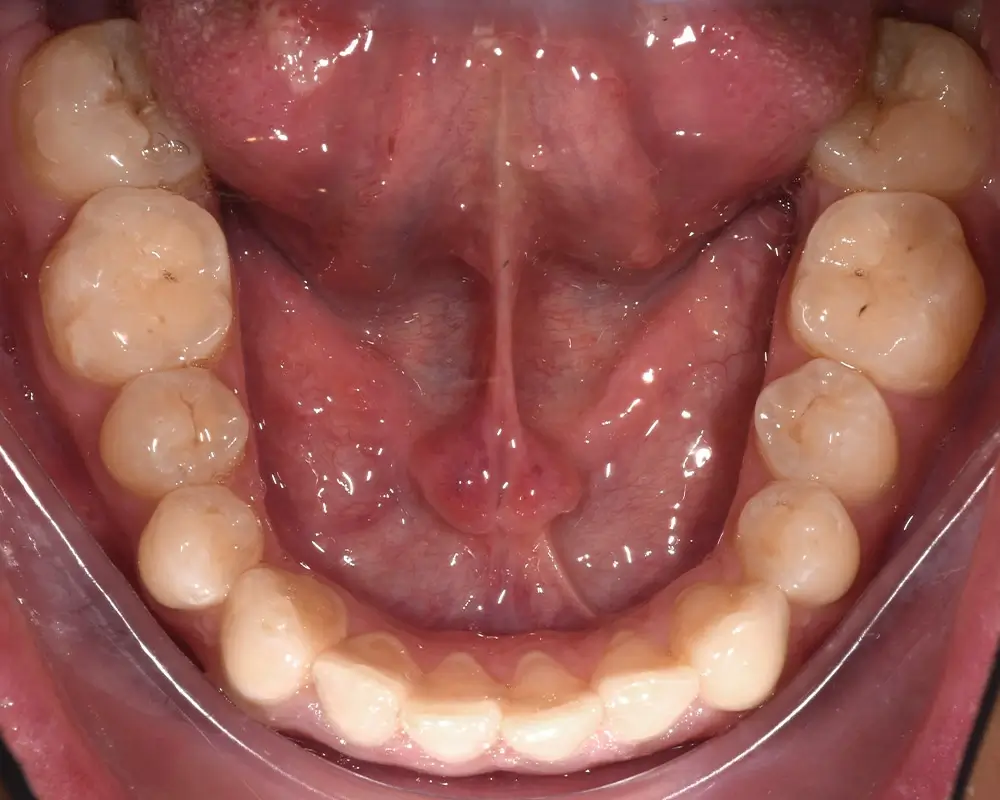

Открытый прикус - Кейс 3

Эффективность устранения дефекта прикуса посредством элайнеров FlexiLigner.

28

Количество кап НЧ

Результаты лечения